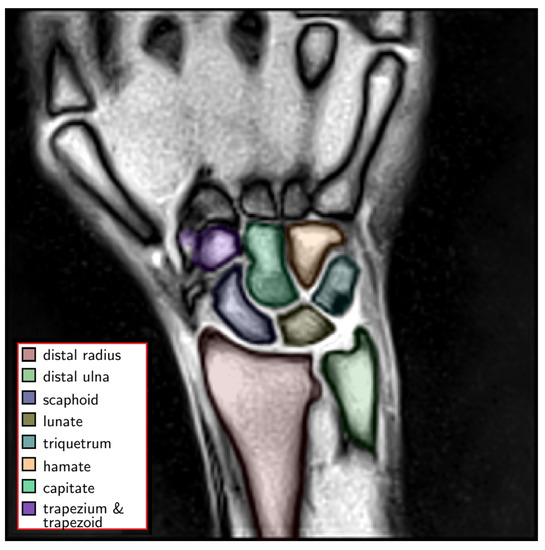

3.4. Assessment of Clinical Applicability in a Patient